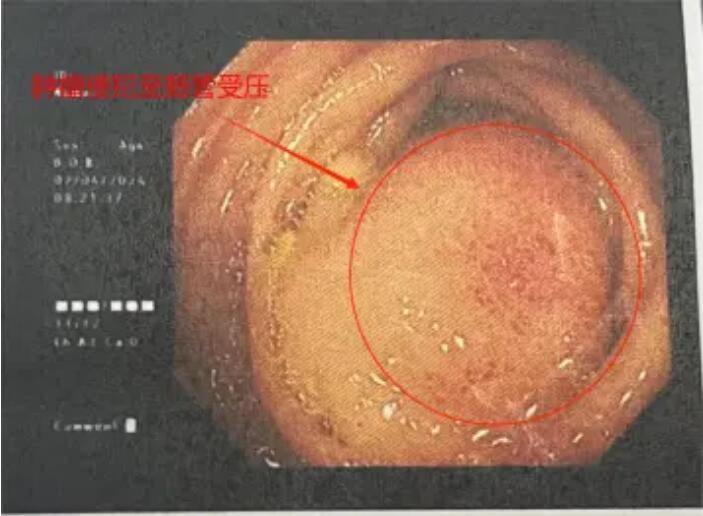

年过六旬的赵大娘(化名)近一月以来间断性出现左下腹疼痛,每次发作呈刺痛,伴食欲减退,排便困难,症状持续加重,门诊查CT回报:左上腹结肠占位性病变,考虑恶性,左肾上腺占位,考虑转移瘤可能(径线34mm*17mm),胃肠镜检查提示:“结肠肿物,结肠黏膜隆起”。赵女士家属拿到检查报告后心急如焚,经多方打听后,赵大娘来到了胃胰脾外科,希望得到救治。翟博教授经评估了患者影像资料后,考虑患者为胰腺体尾部的恶性肿瘤,并累及周围脏器。入院后的增强CT证实了上述诊断。

肿瘤侵犯结肠,肠管受压,造成患者排气排便困难

由于患者瘤体巨大,侵及周围脾、肾上腺、结肠、胃、十二指肠等多个脏器器官,手术难度极高,翟博教授随即请科室主任谭刚教授会诊,基于对患者病情分析及为降低手术风险,完善胰腺三维成像,得以精准定位肿瘤位置及周围血管分布,精准规划手术流程。

谭刚教授仔细研究了赵大娘的病情,认为肿瘤虽然涉及多个脏器,但尚未发生远处转移,为挽救患者生命,谭刚教授毅然决定开腹探查,以期为患者争取最后的治疗机会,经过周密的术前准备,赵大娘躺到了手术台上。术中探查可见胰体尾肿物,累及脾门、侵及结肠脾曲,脾动静脉、胃底及十二指肠,在谭刚教授、翟博教授两位主任的精密合作下,经过3个多小时的艰苦奋战,为赵大娘施行了“根治性胰体尾切除、脾切除、结肠脾曲切除、胃十二指肠修补术,左侧肾上腺切除”的多器官联合切除,患者术后顺利返回病房。目前患者恢复非常顺利,已康复出院。出院时,赵大娘家属激动地表示:“真的没想到这么大的肿瘤还有根治的希望,在切除了这么多器官后,术后还恢复得这么快,感谢普外二团队给了我老伴第二次生命!”。